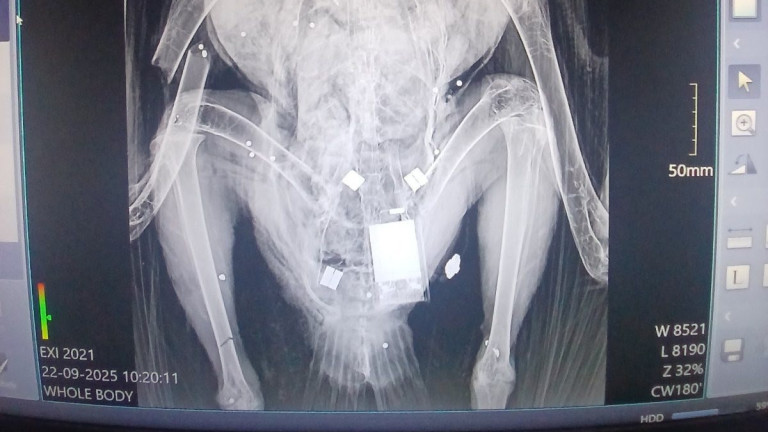

Лешоядът е застрелян на 20 септември, като е бил част от една от трите успешни двойки, които тази година в Котленска планина отгледаха малки - най-успешният гнездови сезон от началото на програмата през 2018 г.

Малкото на женската е настанено в Спасителния център на "Зелени Балкани"